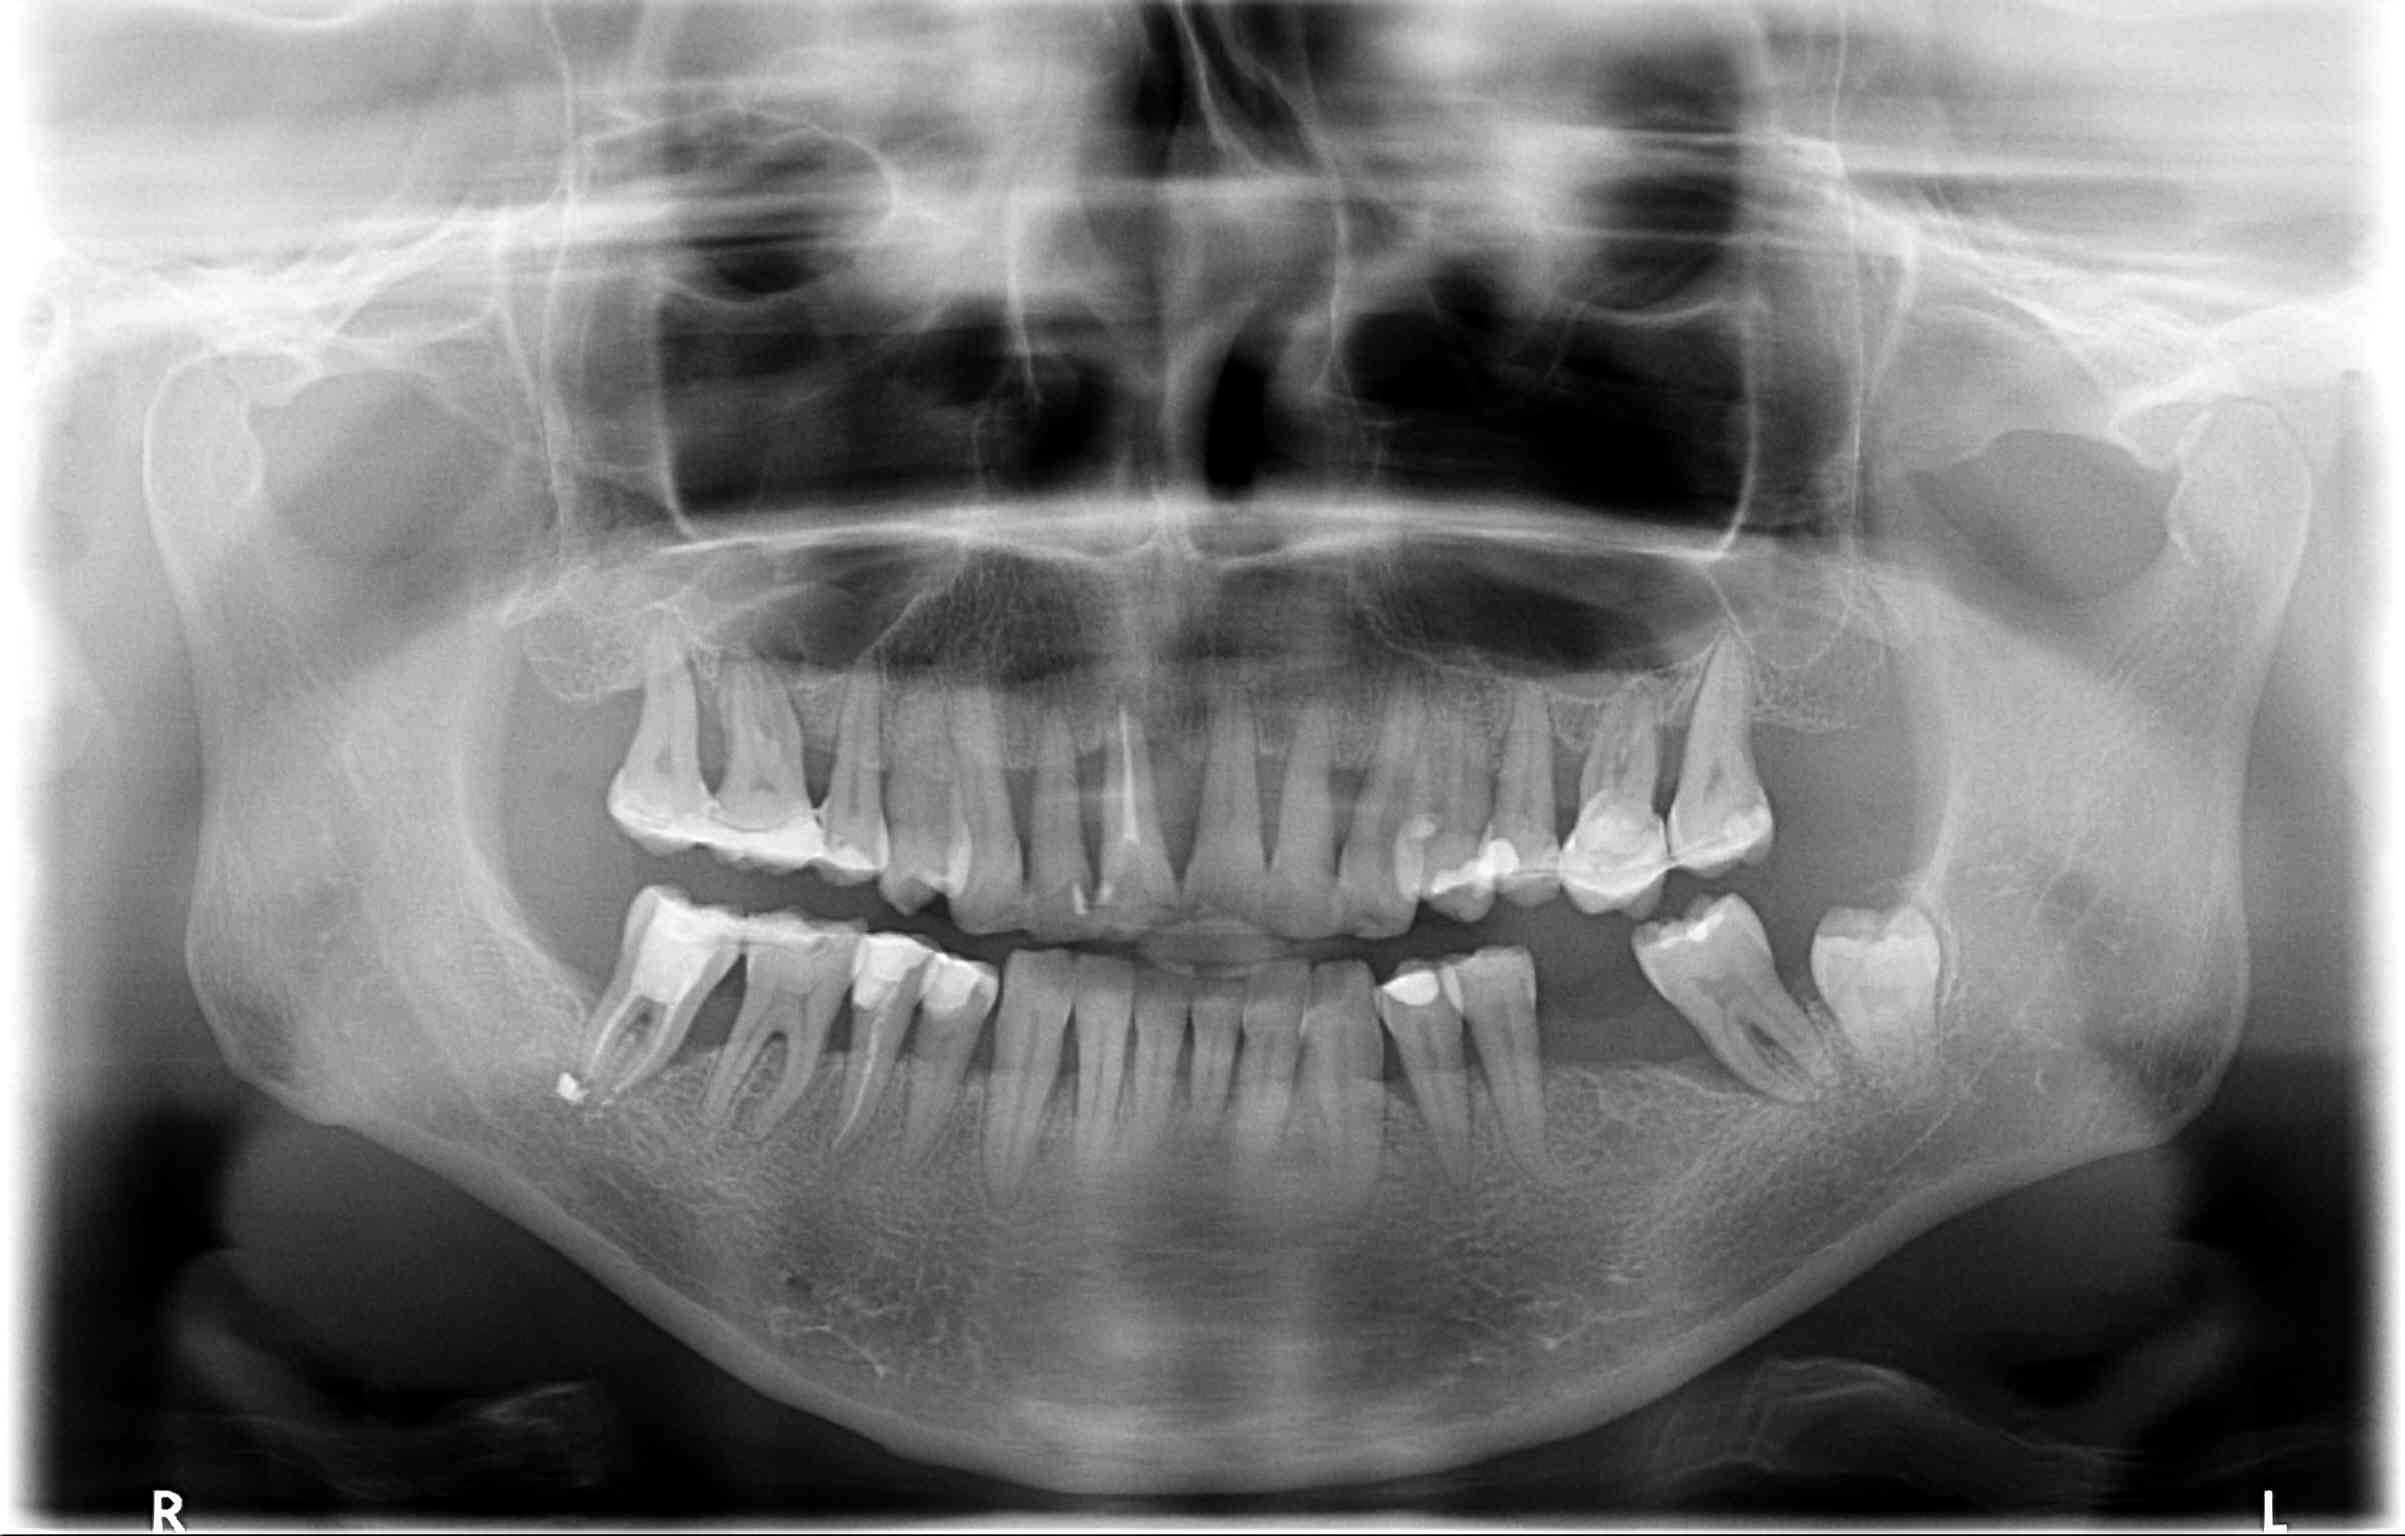

Bogata w płytki i leukocyty fibryna jest stosowana w regeneracji tkanek od ponad 15 lat. Pozytywny wpływ PRF (platelet-rich fibrin) na regenerację tkanek miękkich jest niewątpliwy, bezsporny i częściowo udowodniony w badaniach klinicznych i analizach biochemicznych. Wpływ PRF na regenerację tkanki kostnej jest obserwowany klinicznie, ale nadal niedostatecznie poznany jest mechanizm tego zjawiska.

Platelet- and leukocyte-rich-fibrin has been used in regeneration of tissue for more than 15 years. The positive influence of PRF on the regeneration of soft tissue is undoubtedly, without question and partially proven in clinical studies and biochemical analysis. Influence of PRF on regeneration of bone tissue is observed clinically but the mechanism of this phenomenon is still not sufficiently known.